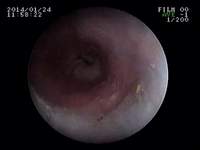

内視鏡のお話(仔牛のあばらぼねガム)

先日、2日前から食欲廃絶のチワワさんが来院しました。そのきっかけが、同居している大型犬のおやつを横取りしたときからとのことでした。話を聞いたら、その後からずっと泡状の液体を吐いているようでした。それは、おそらく唾液をのめなくて突出しているのだと直感しました。

ガムは仔牛のあばら骨ガムだったので、食道停滞を考えました。エックス線を撮影したら、さすがにあばら骨だけあってくっきり咽頭部付近の食道に写っていました。すぐに内視鏡をすすめて処置をはじめたのですが、扁平のガムが食道を拡張させはまり込んで内視鏡鉗子(直径2mm)ではとれませんでした。押して胃内に押し込むことも考えましたがびくともしません。そこで腹腔鏡(硬性鏡)用の鉗子(5mm)を内視鏡と併走させて食道の異物まで到達させ把持することを考え、実施したらなんとかうまくつかめました。場合によっては、開胸手術による食道切開で摘出することも適応になる症例であってもおかしくありませんでした。

これは、今までの経験が生かせた処置ともいえました。麻酔が覚めた本人はケロッとしていて、ごはんを欲しそうな様子でした。この顔をみたとき、ある意味充実感がありました。よかったね、富士ちゃん!

![]() |

食道にはまったガムを腹腔鏡鉗子で取り除いている様子 | 実際とれたあとの食道粘膜の写真(一部炎症とびらんがあります) | 正常の食道粘膜の写真 | 実際とれたあとの写真 (ガムの中にあばら骨があります) |